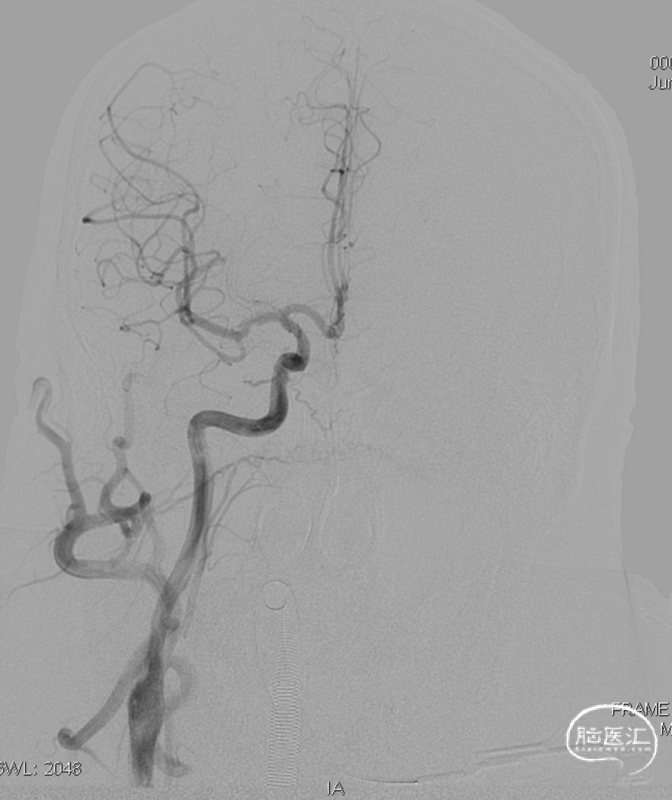

术前CT见左侧眼上静脉扩张

LECA

左侧咽升供血的HCDAVF,逆流至海绵窦,经眼上静脉-面静脉引流。